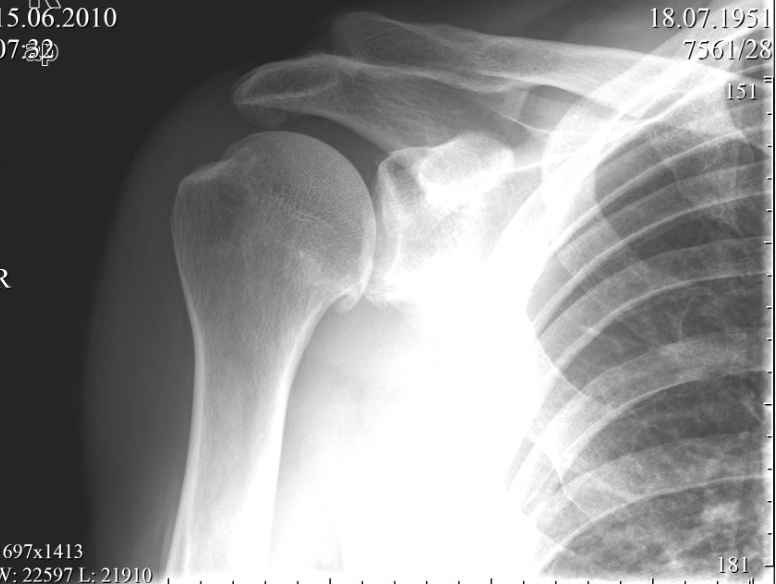

Пациент, мужчина, 59 лет обратился в июне с жалобами на умеренные периодические боли и хруст в области правого плечевого сустава. В анамнезе - 1,5 года назад упал, ударился задней поверхностью локтевого сустава, при отведенной правой руки в плечевом суставе и согнутом в локтевом. Обратился за мед. помощью, по месту жительства, сказали, что ничего страшного, повесили травмированную конечность на косынку.Тогда, в июне 2010года, когда я впервые увидел пациента, он щадил руку, было ограничение объема движений в правом плечевом суставе. Потому я предложил заняться лечебной физкультурой а потом посмотреть достигнутый результат.Сегодня в пациента восстановлен полный объем движений в правом плечевом суставе, боли сохраняются, но не такие выраженные, как раньше.Но при движении правой рукой стоит ТАКОЙ хруст, что слышен на расстоянии. Пальпаторно, при движении правой рукой,ощущается подвижность в акромиально-ключичном сочленении, и боли при отведении в правом плече более 120 градусов.Пациента не устраивает нынешние положение дел с его плечом. Хочет более радикального лечения.Я подумывая об операции, но побаиваюсь за результат. Нужно иссечь рубцы, низвести акромиальный конец ключицы (а она будет "пружинить")и фиксировать крючковидной пластиной к акромиону, не исключается выполнение акромионопластики. Удержит ли пластина и удержатся ли взаимоотношения в акромиально-ключичном сочленении, после удаления пластины?Тут вспомнился разговор с профессором Джолдасом Кулджановым, о необходимости восстановления клювовидно-ключичной связки. Хотелось бы освежить этот разговор в своей памяти и попросить профессора найти время и рассказать еще раз о целесообразности и технике восстановления клювовидно-ключичной связки, ну выслушать мнение коллег по Ортофоруму.С уважением Шушания Батал.

На представленном снимке нет данных за повреждение акромиально-ключичного сустава.

Возможно у вашего пациента было какое-то повреждение АКС. Об этом говорит

состояние небольшого подвывиха, вторая степень - суставные поверхности

находятся друг против друга с небольшим смещением ключицы. Смещение

оценивается по нижней поверхности АКС. Но на рентгеновском снимке бросается

в глаза дегенеративные изменения. Первый из них это остеофит в нижней части

головки плеча (французская бородка) помечен стрелкой. Эта находка говорит о

артрозе плечелопаточного сустава. Вторая находка большой остеофит

акромиального отростка - помечен пунктирной линией. Данная находка говорит о

существующем давлении на сухожилия манжетки вращателей и вероятно разрыв

сухожилий. Rotator cuff syndrome Rotator cuff tear. Полный разрыв сухожилий

может объяснить хруст при движении в плечевом состоянии.